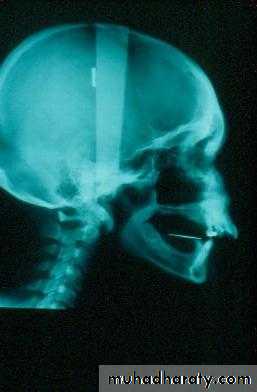

Factors that impact on fit: atrophy

• Atrophy• a. Decreasing bone

b. Increasing soft tissue

1. Atrophya. Decreasing bone

1. Atrophy: accelerated by inflammationa. Infection

b. Poorly fitting dentures … friction

c. Habits … clenching / bruxism